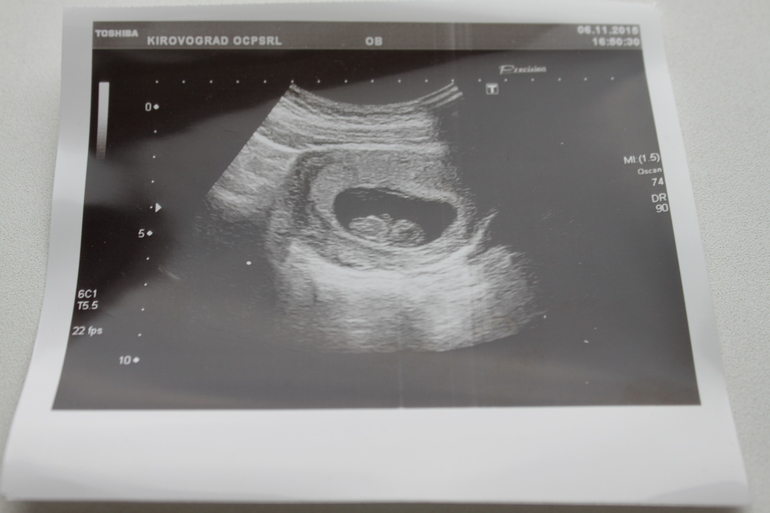

Направила нас доктор на УЗИ для уточнения срока Б перед скринингом. На первом УЗИ только папа наш видел ПЯ, я была в таком волнении, что и попросить показать забыла.

А теперь и я ВСЕ увидела! Делали в пятницу (6.11) вечером. Нам 9 неделек, наш КТР 23,2 мм, сердечко тарабанит вовсю)))) Узист сказал, что по тому, что он может увидеть на этом сроке, все в норме.